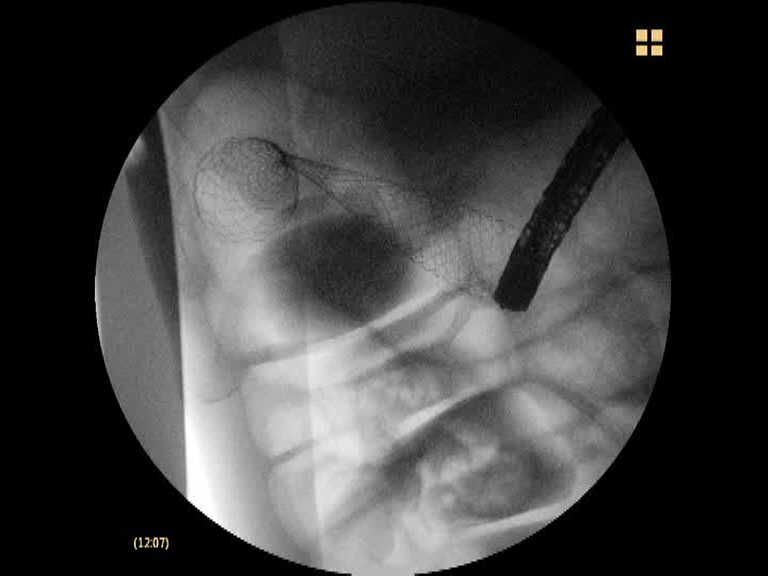

Paciente de 81 años de edad con múltiples patologías (intervenido de neoplasia de la unión gastroesofágica en 2010, adenocarcinoma de próstata, IRC severa, etc..), que presenta un cuadro consitucional severo con anemia importante normocítica y cuadros suboclusivos. En la colonsocopia realizada se aprecia una lesión estenoante, infranqueable con el endoscopio en el ángulo hepático. Ñas biopsias confirman el diagnóstico de adenocarcinoma de colon. En el TAC realizado se aprecia un engrosamiento circunferencial estenosante junto a distensión de asas de i. delgado, sin metástasis a distancia. Dada la edad y la patología severa asociada, junto con la clínica suboclusiva, se decide tratamiento paliativo con un stent metálico no recubierto de 12 cm de longitud.